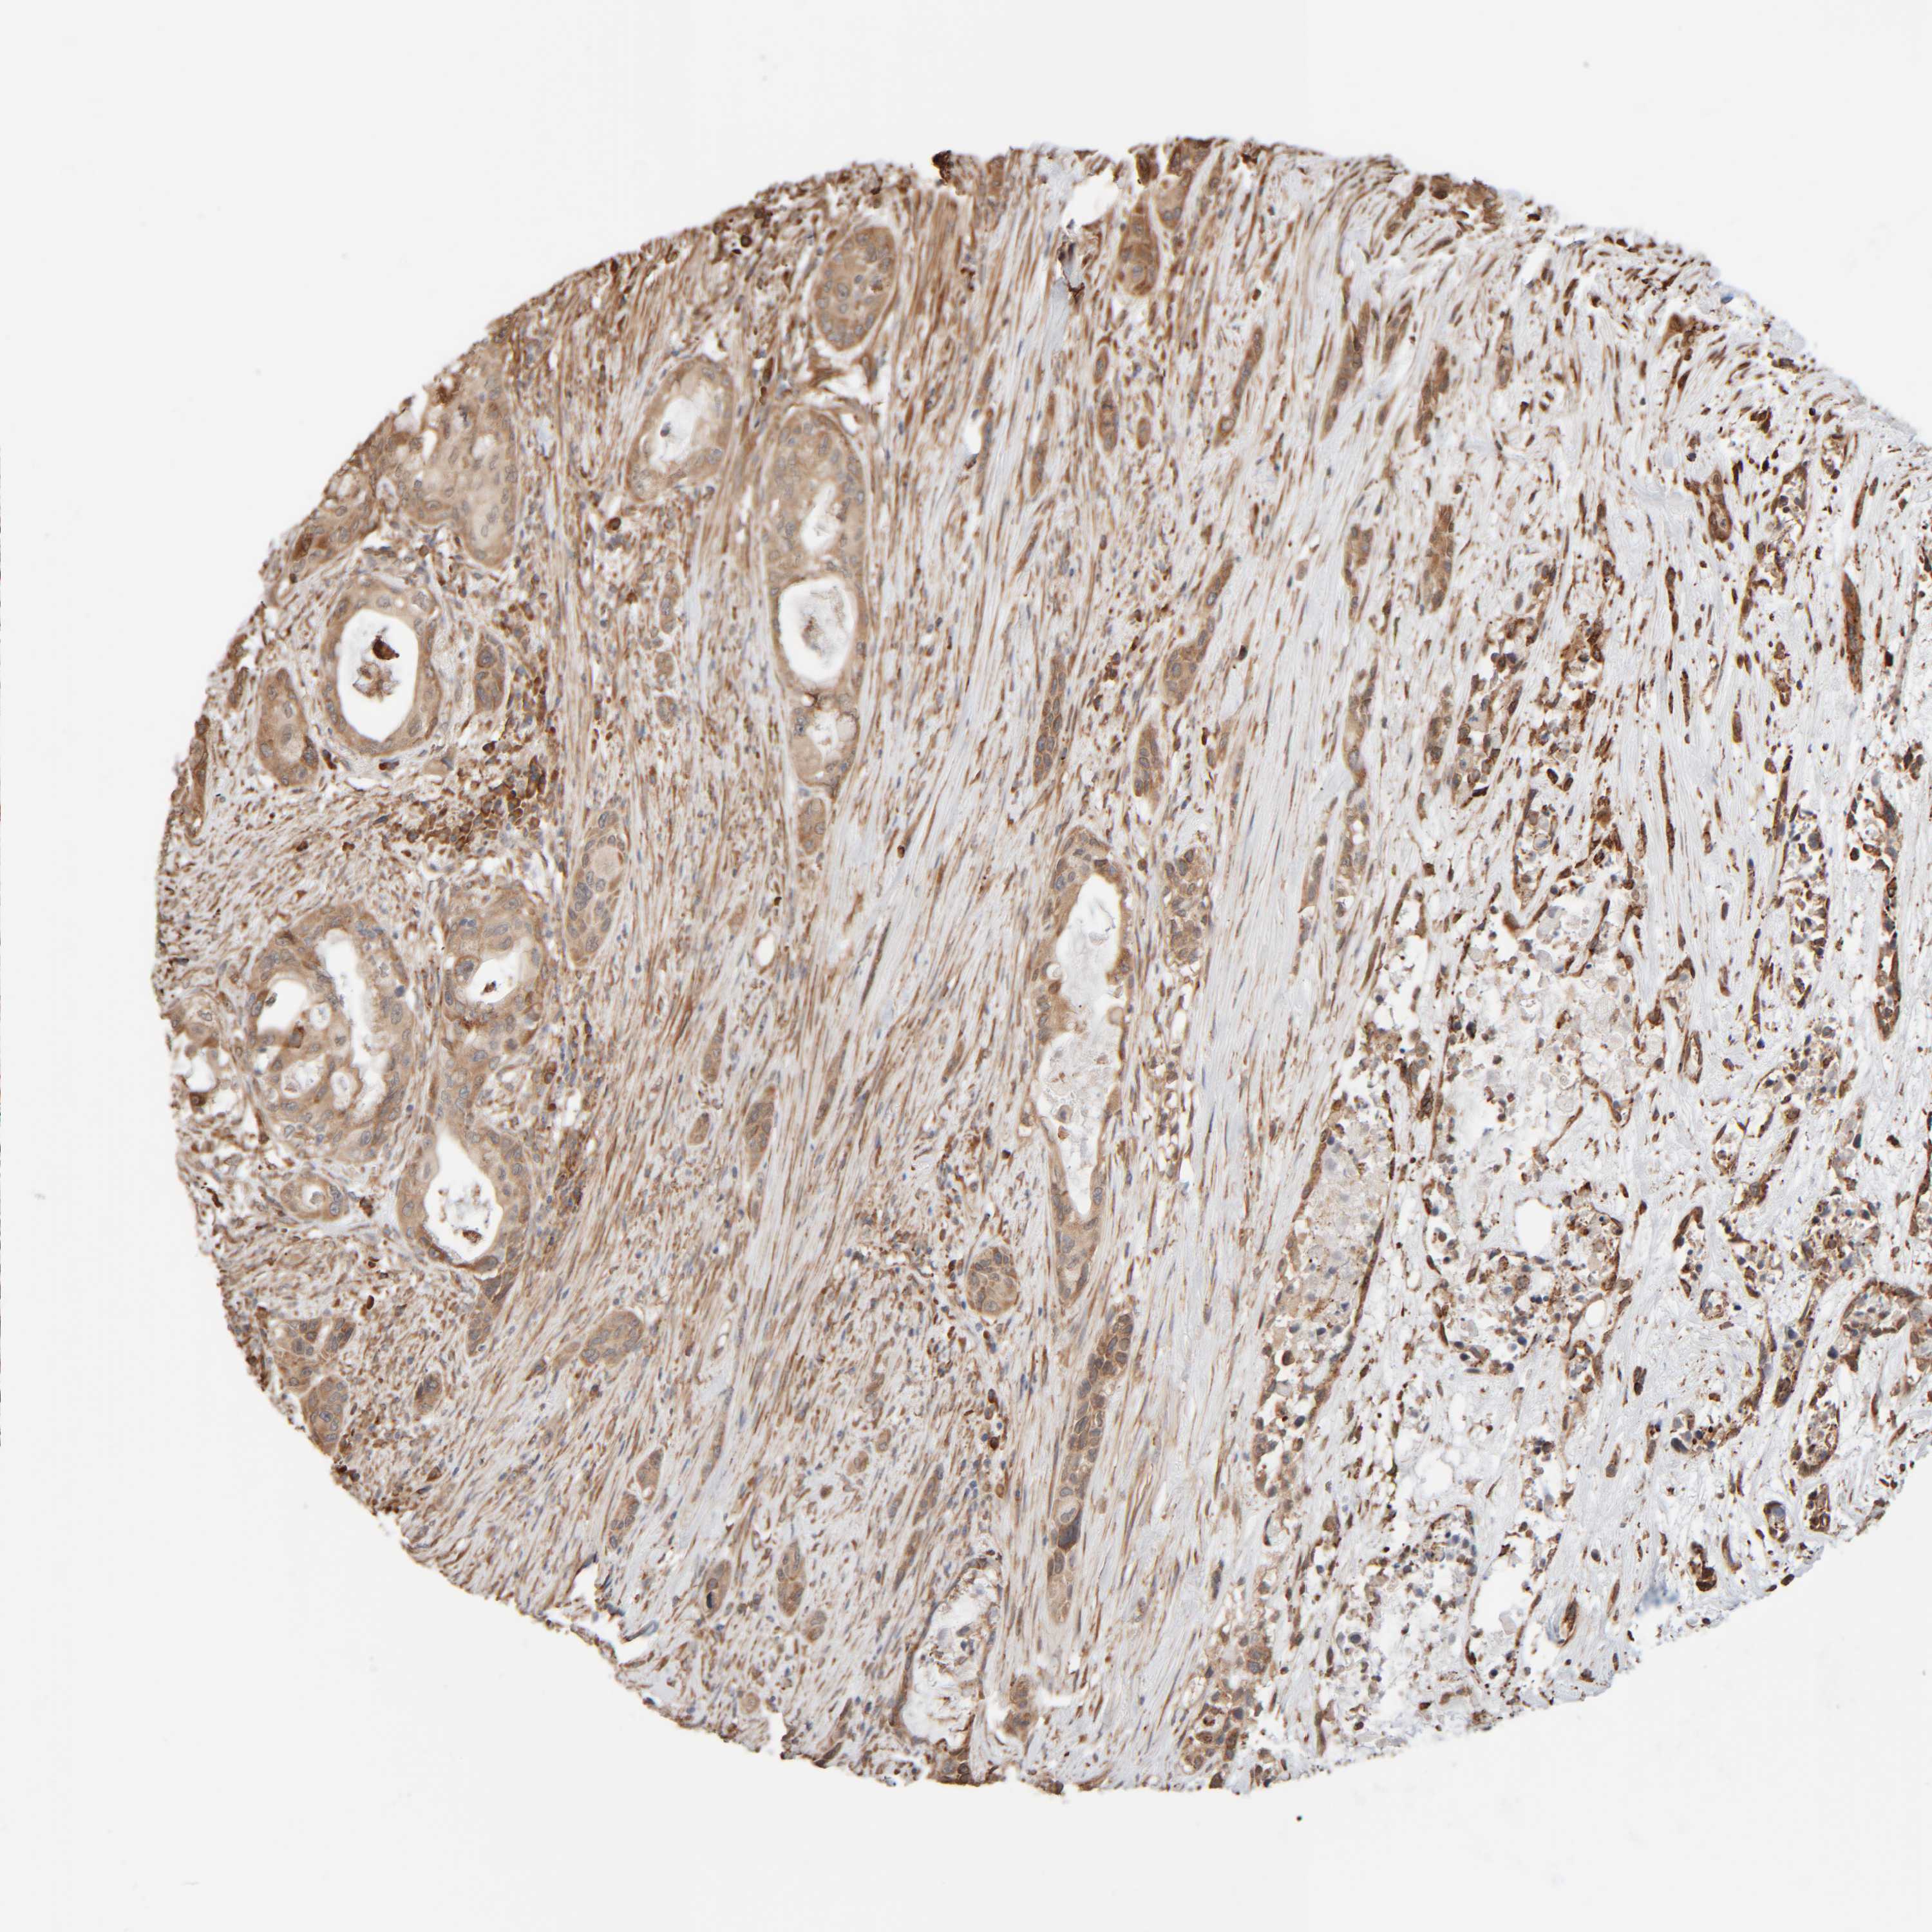

PANCREATIC CANCER - Protein expressioni

A mouse-over function shows sample information and annotation data. Click on an image to view it in a full screen mode. Samples can be filtered based on level of antibody staining by selecting one or several of the following categories: high, medium, low and not detected. The assay and annotation is described here.

Note that samples used for immunohistochemistry by the Human Protein Atlas do not correspond to samples in the TCGA dataset.

Antibody stainingi

Antibody staining in the annotated cell types in the current human tissue is reported as not detected, low, medium, or high, based on conventional immunohistochemistry profiling in selected tissues. This score is based on the combination of the staining intensity and fraction of stained cells.

Each image is clickable and will lead to virtual microscopy that enables deeper exploration of all samples and also displays staining intensity scores, fraction scores and subcellular localization as well as patient and tissue information for each sample.

Antibody HPA021658

Staining

High

Medium

Low

Not detected

Intensity

Strong

Moderate

Weak

Negative

Quantity

>75%

75%-25%

<25%

None

Location

Nuclear

Cytoplasmic/membranous

Cytoplasmic/membranous,nuclear

Adenocarcinoma, NOS